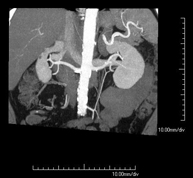

Renal artery CT angiography

A non-invasive diagnostic test that involves studying the renal arteries by obtaining high-definition anatomical images using CT (computed tomography) equipment and iodinated contrast. With the aid of workstations specialised for arterial studies, the image quality supports 2D and 3D reconstructions. This test is recommended, for example, in patients suffering from refractory hypertension that does not respond to processing, in patients with kidney damage in order to obtain a pre-surgical ‘vascular’ map, etc.